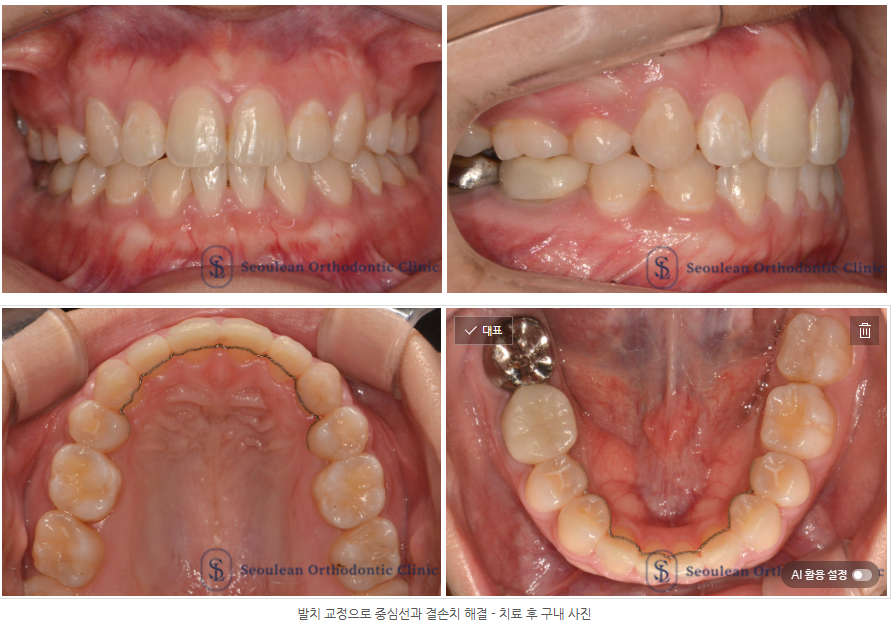

치료 결과|배열·중심선·교합의 조화로운 회복

교정 치료 종료 후 다음과 같은 개선을 확인할 수 있었습니다.

덧니 개선: 고른 치열로 배열되어 전체적인 인상이 부드러워졌습니다.

상·하악 중심선 일치: 미소 시 얼굴 정중선과 자연스럽게 조화를 이루게 되었습니다.

교합 안정화: 선천적 결손으로 인한 교합 불균형이 개선되었습니다.

심미성 향상: 기능적 안정성과 함께 자연스럽고 단정한 미소를 회복하였습니다.

환자 본인뿐 아니라 보호자 역시 치료 결과에 높은 만족도를 보였습니다.